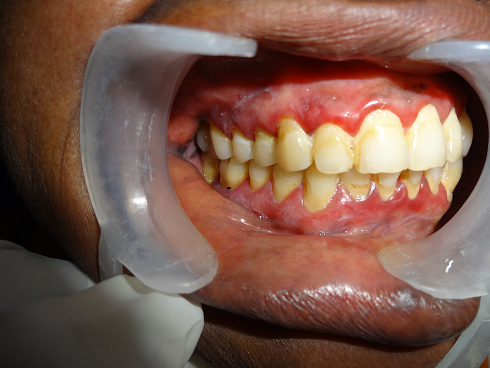

desquamative gingivitid